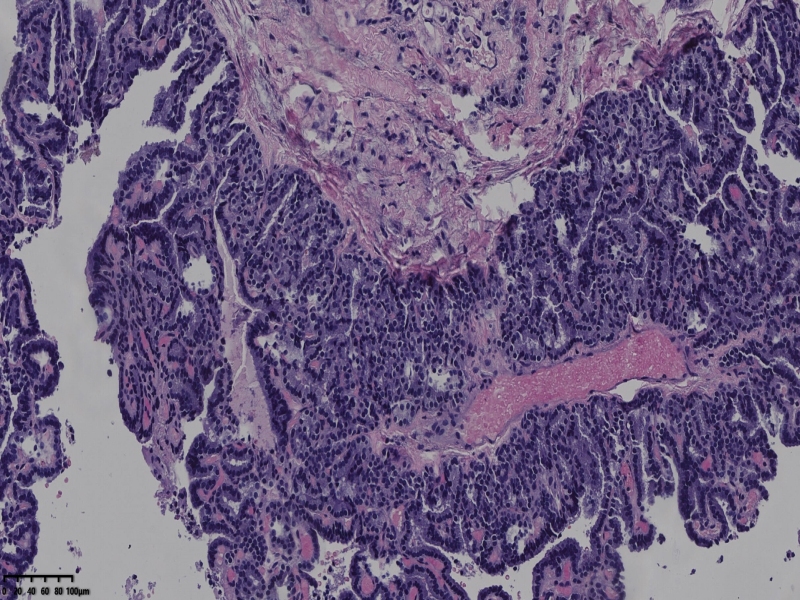

男、69、甲状腺左叶肿物,部分为囊性,囊内可见乳头状结构,上皮核重叠,没有核沟,没有毛玻璃样改变,没有核内假包涵体。255427

部分区域瘤组织与周围甲状腺组织分界明显,没有包膜样结构,滤泡结构为主,细胞异型明显。

会诊结果:(左叶甲状腺近峡部)甲状腺肿瘤,考虑为具有RAS核的乳头状癌,建议免疫组化及基因检测。